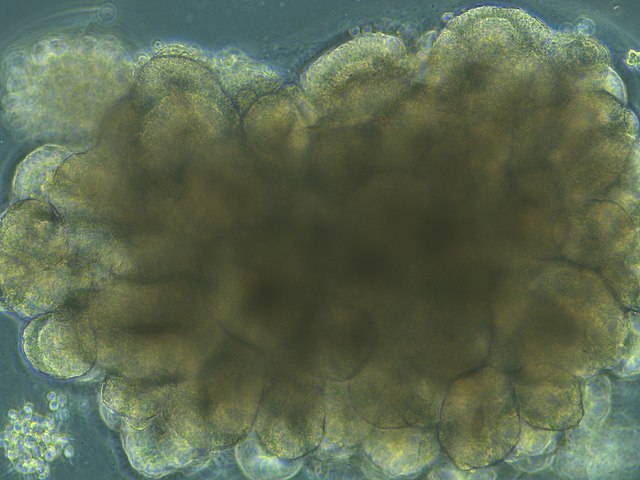

Enter brain organoids. These are three dimensional models made from clusters of human stem cells grown in the lab. They aren’t “brains in a dish” – they can’t function or think independently – but they can help us develop a deeper understanding of how the brain works and even why it doesn’t always work as well as we’d like.

The team – with CIRM funding – took skin tissue from healthy individuals and, using the iPSC method – which enables you to turn these cells into any other kind of cell in the body – they created brain organoids. They then studied both the physical structure of the organoids by examining them under a microscope, and how they were functioning by using a probe to measure brain wave activity.

In a news release Dr. Ranmal Samarasinghe, the first author of the study in the journal Nature Neuroscience, says they wanted to do this double test for a very good reason: “With many neurological diseases, you can have terrible symptoms but the brain physically looks fine. So, to be able to seek answers to questions about these diseases, it’s very important that with organoids we can model not just the structure of the brain but the function as well.”